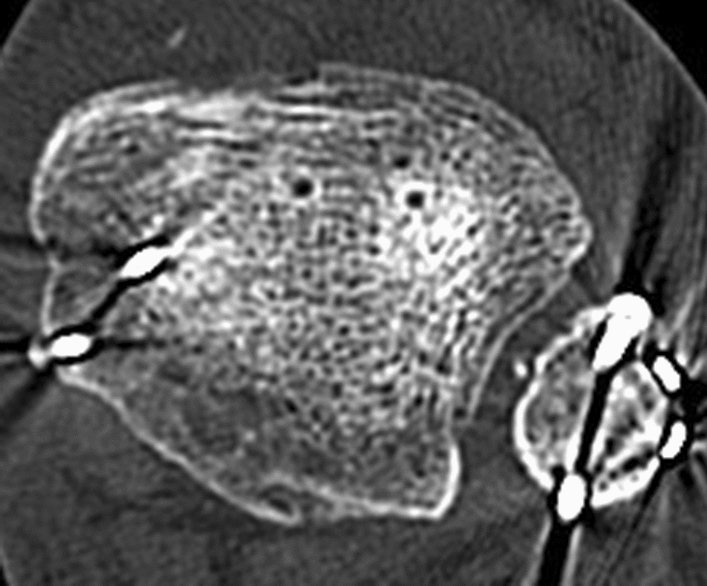

A split lower leg cast was applied for 6 weeks postoperatively. The surgical wounds healed uneventfully. In the postoperative period, the patient showed progressive paresthesia, mainly at the plantar surface of the foot, persisting swelling of the left ankle and development of a clawing of all toes, including a cockup deformity in the great toe. Sensation was diminished in the toes and almost absent in the area of the great toe and the first interdigital web space. The follow-up CT scan 2 months postoperatively documented a nearly anatomic reduction of all fragments, including the distal fibula into the fibular notch (Fig. 5). At that time, the syndesmotic screw was removed.

Fig. 5.

Postoperative CT control. a axial scan; b frontal scan